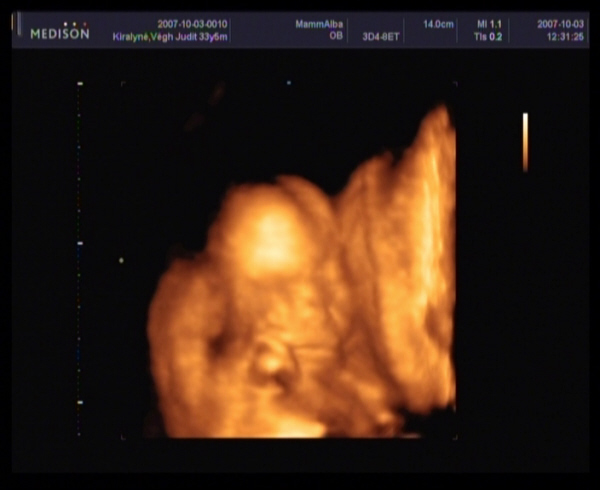

Megjöttem a 4D-ről.

Szupi volt, bár sajna kicsi bogaram állandóan vagy a néhlepénybe furta az arcát, vagy a kezecskéit tette az arcocskája elé, és elég nehéz volt rendesen elkapni.

Amugy minden rendben van, 20 hetesnek megfelelő.

És végre a lábaközét is megmutatta nekünk.

Szerintem kislány!Én látom a szoknyáját :lol: :lol: :lol: :lol:

Édik a képek!